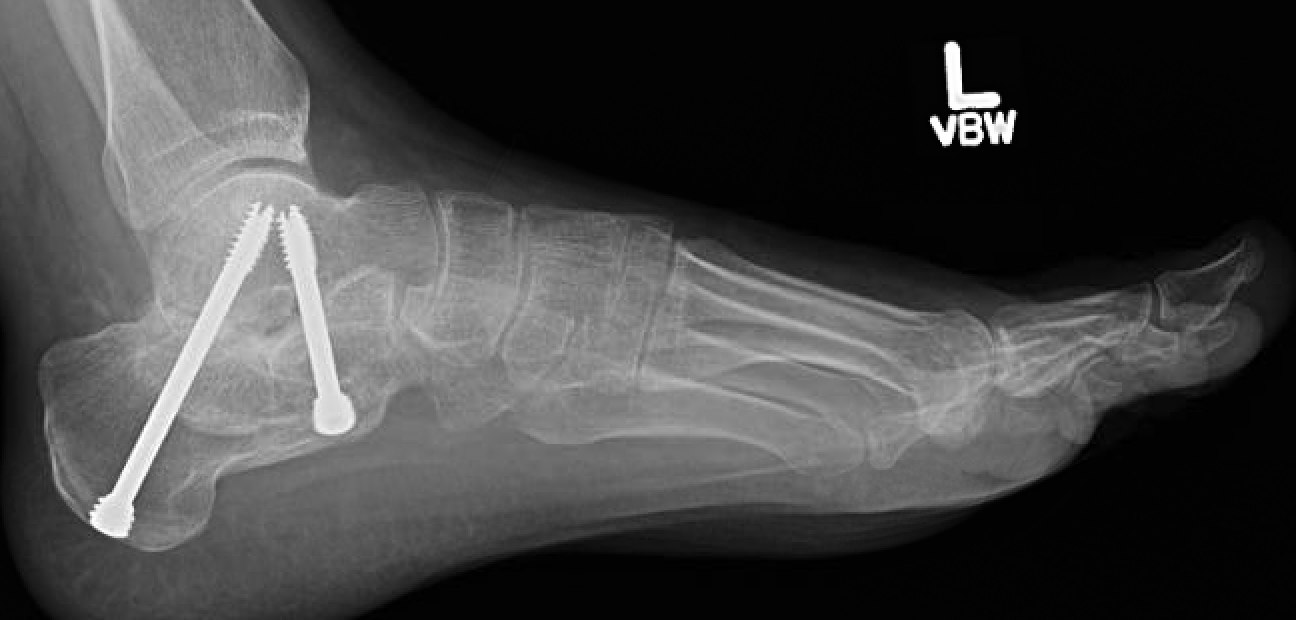

Subtalar Fusion

Subtalar+fusion+X+screws.png